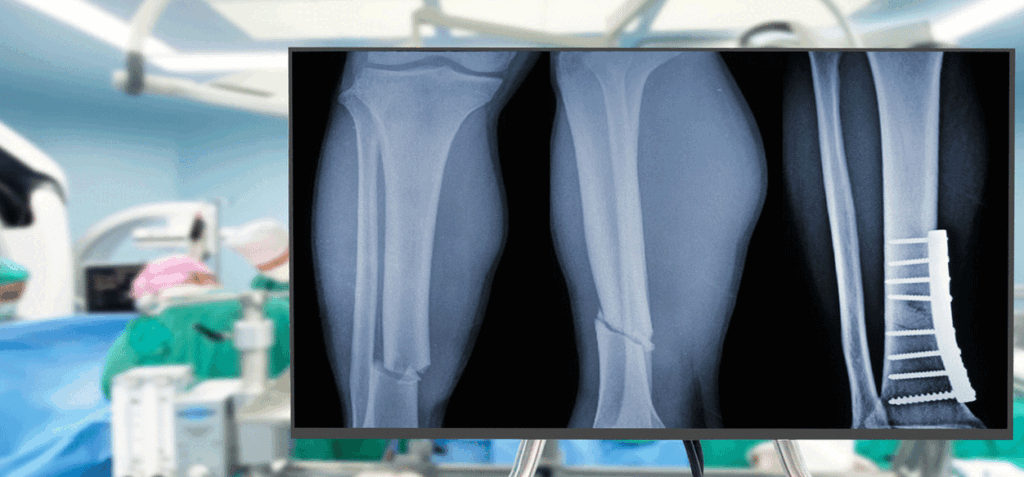

Gracias a su tecnología adhesiva, el pegamento, bautizado como Bone 02, ha logrado unir y fijar en unos pocos minutos distintos fragmentos óseos mediante una incisión de 2 a 3 centímetros que resulta mínimamente invasiva.

El material, inspirado en las ostras, representa un avance significativo respecto de los procedimientos tradicionales, que utilizan placas de metal para recuperar los huesos atendidos.